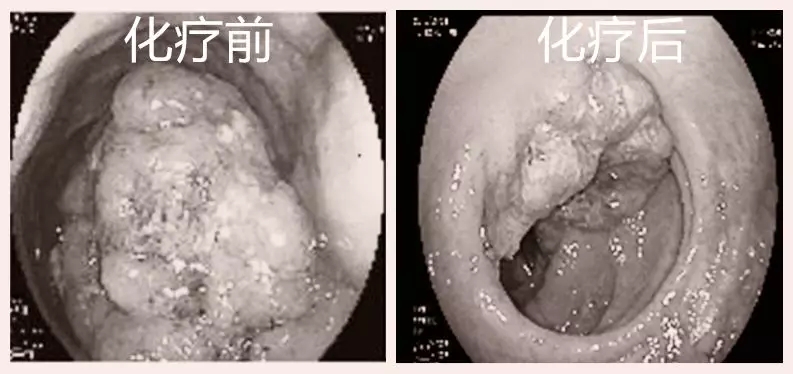

化疗后直肠肿瘤明显退缩

化疗后直肠肿瘤明显退缩